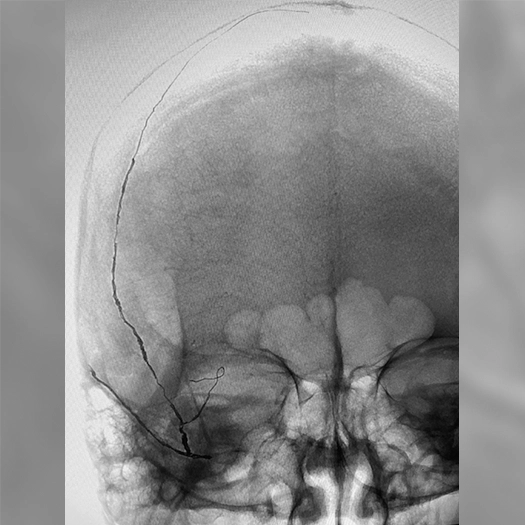

angiogram of embolization coils in a vessel

MMA embolization with 3 SwiftPAC coils: 45 cm, 15 cm, 30 cm

MMA Embolization

• SwiftPAC coils offered embolization

• MIDWAY 43 provided delivery support

• BENCHMARK071 provided stable, reliable access

• A combo designed to support confident, controlled delivery (see case to left)